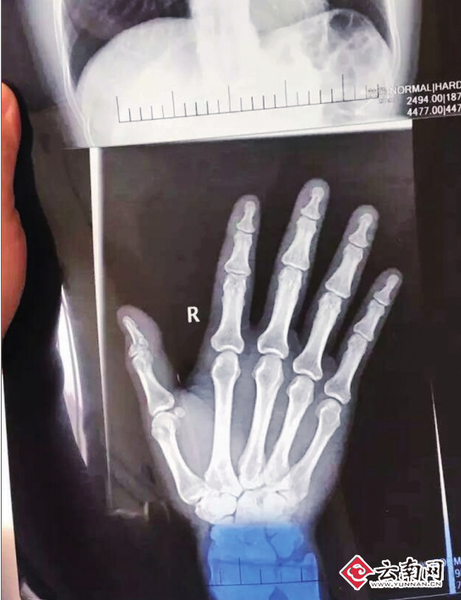

黄敏说,被打后,他立即报了警。除身上多处软组织挫伤外,伤得最严重的是右手大拇指粉碎性骨折,一掌骨骨折。他到云南省第三人民医院住了7天院,医生说无法手术,只能用夹板固定,也不吃药,待其自然修复,至少要3个月以上,右手大拇指还有可能伤残。